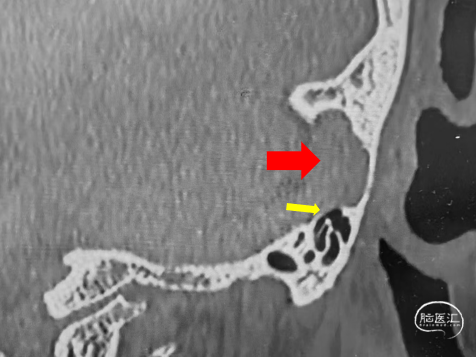

红色箭头示静脉窦憩室

➤CT

乙状窦憩室

高位颈内静脉